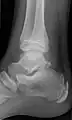

Ankle

Accessory bones at the ankle mainly include:

- Os subtibiale, with a prevalence of approximately 1%.[14] It is a secondary ossification center of the distal tibia that appears during the first year of life, and which in most people fuses with the shaft at approximately 15 years in females and approximately 17 years in males.[14]

- Os subfibulare, with a prevalence of approximately 0.2%.[15]

Os trigonum (further described below) may also be seen on an ankle X-ray.